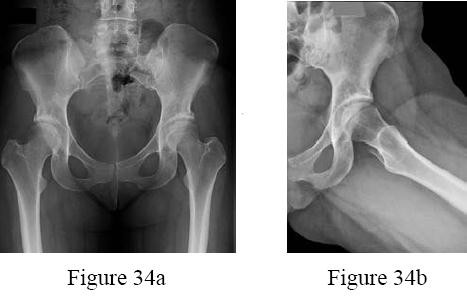

A 13-year-old overweight boy presents with a 3-week history of right groin and knee pain. He walks with a limp. On examination, when his right hip is flexed, it obligatorily externally rotates. Radiographs show a slip of the proximal femoral epiphysis. Which radiographic line is used to diagnose this condition?

Explanation

The clinical scenario describes Slipped Capital Femoral Epiphysis (SCFE). Klein's line is drawn along the superior edge of the femoral neck on an AP pelvic radiograph. In a normal hip, this line should intersect a portion of the lateral capital femoral epiphysis. In SCFE, the line passes superior to the epiphysis or intersects less of it compared to the contralateral normal side (Trethowan's sign).